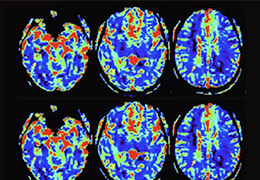

Eclipse 成像智能功能提供强大的处理能力和最佳质量的影像,同时减少质量错误并提高剂量效率。

凭借 AI、专有算法和先进的影像处理能力,提供出色的影像质量和无与伦比的诊断信心。

与标准影像处理相比,智能降噪功能可使客户降低辐射剂量,而不会损失影像质量。这在新生儿和儿科成像中尤其重要,在这种情况下以尽可能低的剂量成像至关重要。

提供相配视图选项,以减少所需的曝光次数,并提供更清晰的感兴趣区域视图。